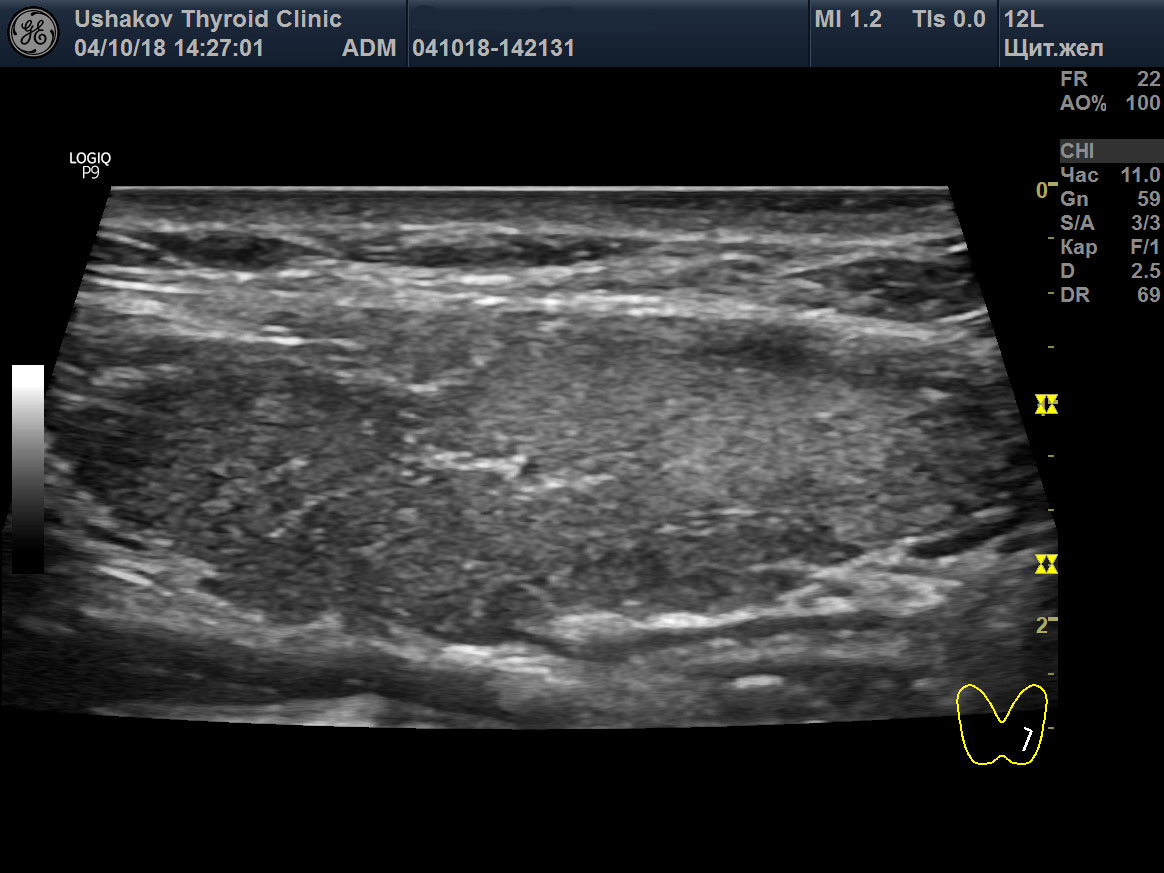

8. Сегменты щитовидной железы. Иммунный процесс в долях и перешейке ЩЖ часто протекает в пределах отдельных сегментов – малых (долек), средних (групп долек) и крупных, что определяется при УЗИ (

рис. 5). Обособленное развитие изменений (деструкция с последующей лимфоцитарной инфильтрацией и пролиферацией) в сегментах разных уровней – признак сегментарной нервной регуляции, способствующей обособленной (сегментарной) активизации перенапряжения и истощения тиреоидной ткани. Только локальное (в сегменте) изменение клеток ЩЖ ведёт к обособленной (сегментарной) активности иммунной системы – распознаванию и проникновению лимфоцитов в сегмент ЩЖ с изменённой тканью. Непосредственное нервное влияние на тиреоидные и иммунные процессы в отдельных сегментах ЩЖ реально и значительно достовернее, чем неподтверждённое и мало достоверное предположение об избирательной агрессии иммунной системы.

Рисунок 5 Левая доля ЩЖ пациентки 35 лет (продольная проекция; режимы В и ЭДК). В краниально-дорсальном крупном сегменте определяется умеренно гипоэхогенная ткань; в вентральном крупном сегменте – изоэхогенная ткань. Заметна чёткая граница между сегментами – гиперэхогенные тяжи соединительнотканной природы. В изоэхогенной зоне интенсивность кровотока в малой степени усилена, в гипоэхогенной – ослаблена (из-за истощения ткани).